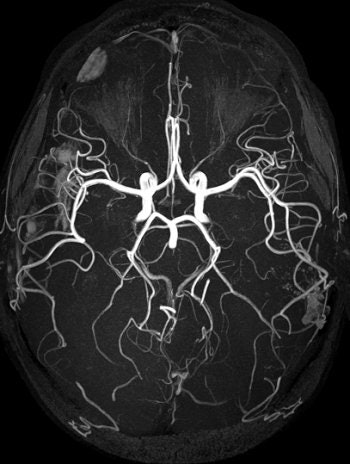

![]() |

| TOF MRA on 3-tesla scanner offers significant vessel detail. Protocol: SENSE x2, 150 slices, 1,024 matrix, 0.25 x 0.45 x 0.6 mm, scan time of six minutes. Image courtesy of Philips Medical Systems North America and University of Bonn, Germany. |